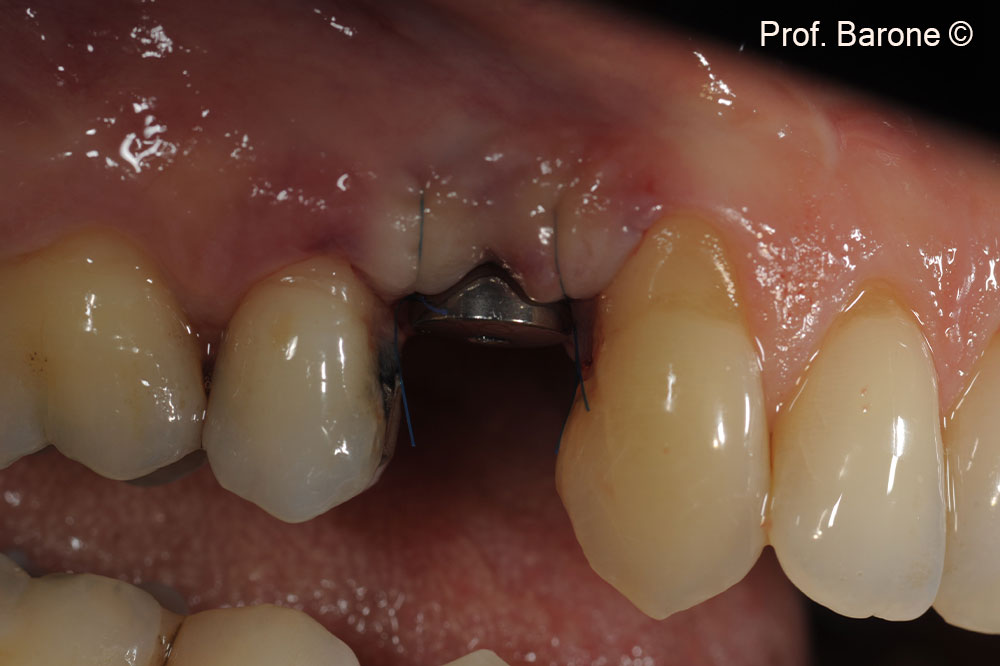

Clinical pre-operative frontal view

Clinical pre-operative lateral view of the tooth #24 (gingival recession and a fistula can be observed)